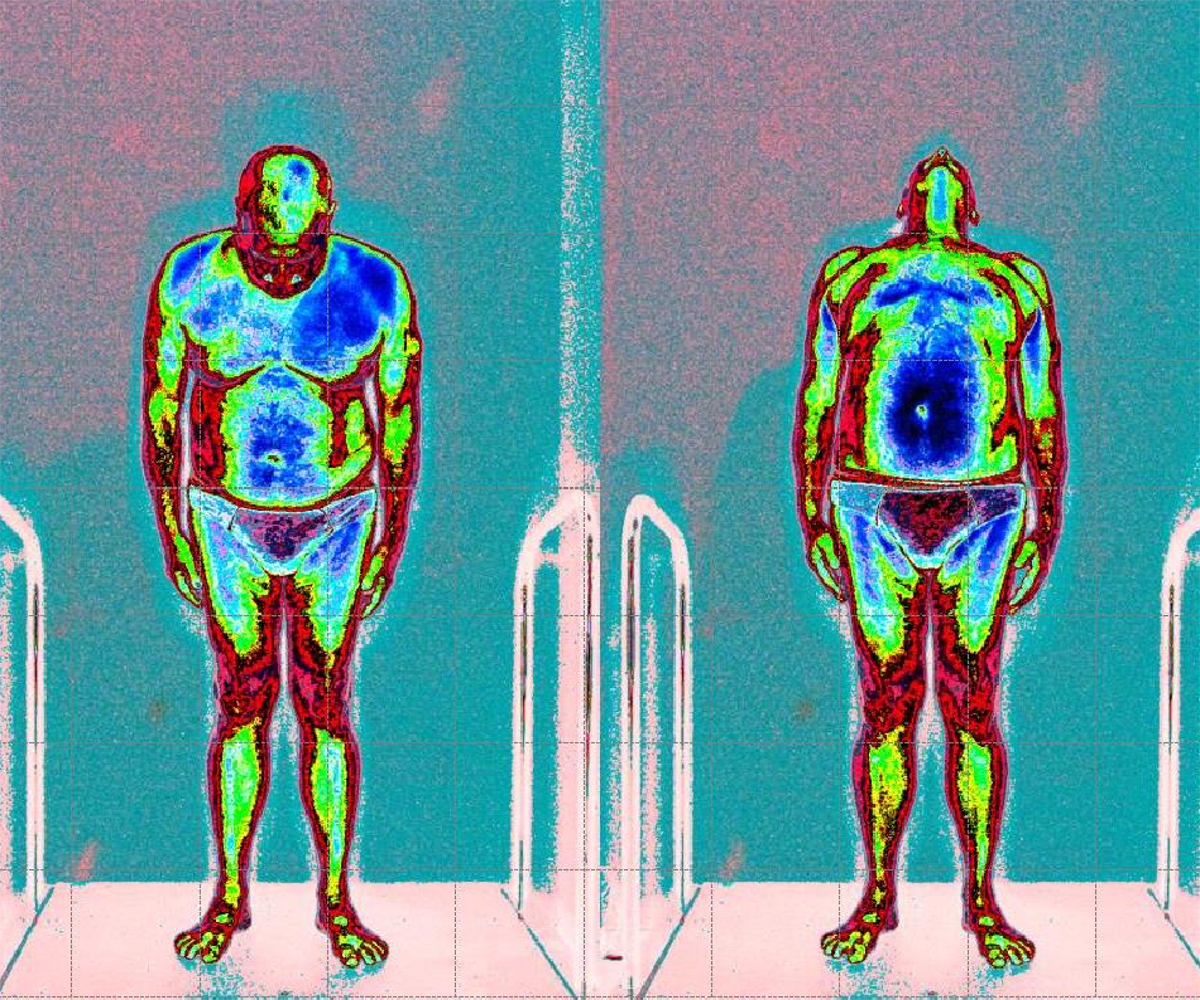

In questa immagine possiamo vedere il cliente paziente con lombalgia acuta causa discopatie multiple

Prime foto maggior tensione globale della muscolatura anteriore (colore blu scuro)

Dopo il trattamento con Renovatio, riduzione netta della tensione muscolare globale (colore azzurro, normalità di tensione)

Sintomatologia riduzione del dolore e maggior flessibilità del tronco.

Leggenda: colore rosso inattivazione tensione muscolare

Verde, minima tensione muscolare

Azzurro normale tensione muscolare

Blu scuro, aumento della tensione muscolare